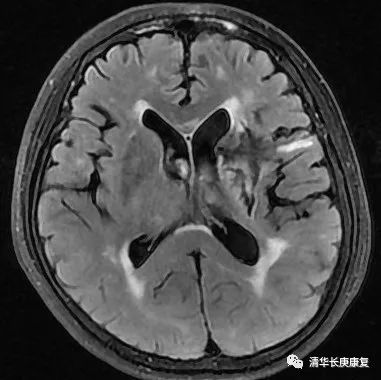

1 头颅 MRI:左侧基底节区脑出血